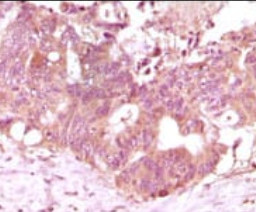

IHC    1/200 - 1/1000